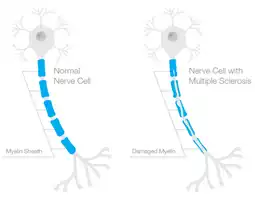

- Multiple sclerosis (MS), a progressive and incurable condition caused by the combination of an individual's genetic influences and environmental circumstances.[4] It occurs when the myelin sheath of the nerve cells becomes damaged.[13] As the myelin sheath is responsible for protecting the nerves and conducting rapid impulses between them, any damage to this lipid-rich layer will result in delayed and interrupted nerve impulses to and from the brain.[14]